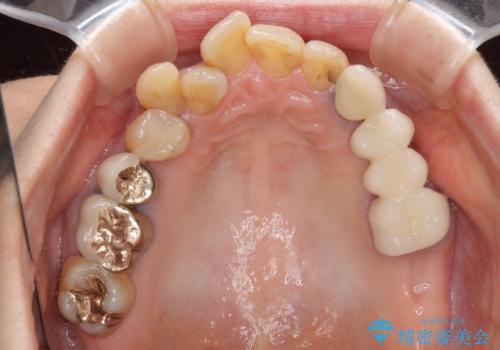

- 奥歯が痛いことを主訴にご来院された患者様です。入院してしまい、治療を2年間放置してしまったとのことでした。

左上は、抜歯とブリッジ治療を行いました(抜歯前に医師と対診)。

左下は、現在も抗がん治療を続けているため、観血的処置(インプラントなどの外科)はなるべく避けたいとのことで入れ歯を希望されました。それに伴い、入れ歯を支える歯のクラウンやりかえも行いました。

患者様はインプラント等の外科処置は希望されなかったため、セラミックと義歯で治療を行いました。

義歯を製作する際は、支えとなる歯の治療も同時に行うことで、義歯の製作が容易になります。

今回もそのように製作したところ、適合がよく安定のよい義歯になりました。患者様本人も使っていて全く痛くないとのことで、追加の調整もなく使用して頂いてます。患者様には、大変満足して頂きました。